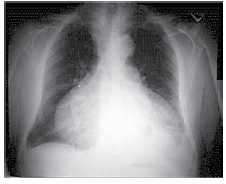

Homem de 62 anos, com história de insuficiência cardíacagrave, é internado devido um quadro dispneico. Pressão arterial: 140 x 115 mmHg, pulso: 122 bpm; ausculta pulmonar: crepitações até ápices bilateralmente. Radiografia de tórax é realizada e mostrada a seguir.

Em relação ao quadro clínico, é correto afirmar: